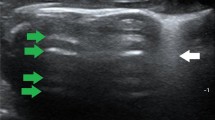

Comparison of lung ultrasound images with gross anatomical and pathological results at corresponding time points revealed the following: Normal lungs showed A-lines and a maximum of 2 B-lines on ultrasound, with normal gross anatomy and pathology. Minor PBLI presented with ≥ 3 well-spaced B-lines on ultrasound, scattered punctate lesions (0.5 cm x 0.5 cm) or occasional (≤ 2) patchy hemorrhages (1.5 cm x 1.5 cm) on gross examination, and pathological findings of interstitial edema and inflammatory cells, with some alveoli ruptured and fused. Moderate PBLI showed coalescent B-lines on ultrasound, scattered punctate lesions (1.5 cm x 1.5 cm) or occasional (≤ 2) patchy hemorrhages (3 cm x 3 cm) on gross examination, and pathological findings of disorganized alveolar structure, with approximately 50% interstitial edema and inflammatory cells. Severe and above PBLI exhibited a tissue-like pattern on ultrasound, with gross examination showing significantly distended and glossy lungs, diffuse large patchy hemorrhages, and pathological findings of > 50% interstitial edema and inflammatory cells, loss of alveolar structure, and numerous red blood cells (Fig. 2 and Supplementary Figs. 1–3).

Correspondence between lung pathology, gross anatomy, and ultrasound images. Ultrasound. White arrows: A lines. Red arrows: B lines. Continuous-line arrows: coalescent B lines. Oval: tissue-like pattern. Gross anatomical manifestations of PBLI in varying degrees. Yellow circle: Partial lung tissue of HE staining. HE staining of lung tissue (200×). Yellow arrows point to inflammatory cells. Green arrows point to red blood cells. Blue arrows point to pulmonary interstitial edema. Black arrows point to alveolar rupture.